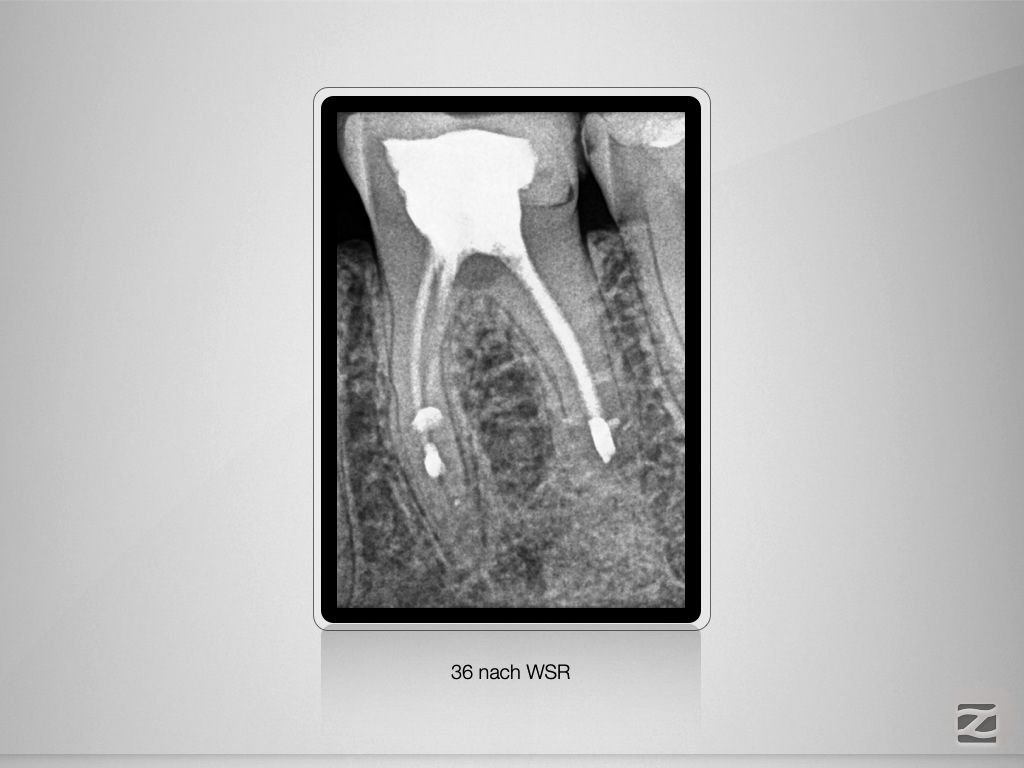

36D.001